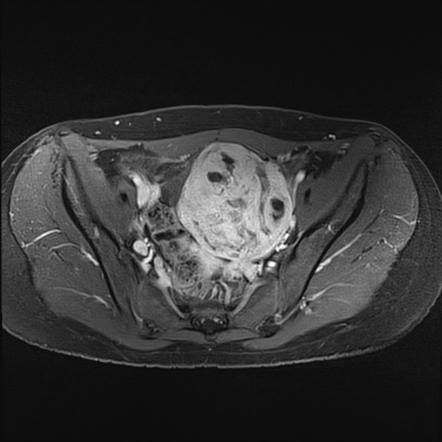

Rhabdomyosarcoma, MRI - Stock Image - C030/6339 - Science Photo Library

www.sciencephoto.com

www.sciencephoto.com

rhabdomyosarcoma mri